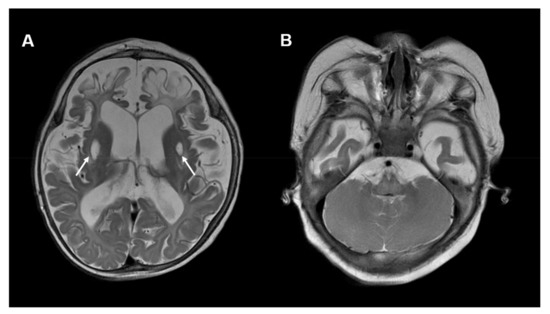

An example of imaging findings in COQ7 deficiency is depicted in Figure 4.

Figure 4.

Neuroimaging in COQ7 deficiency: (A) Brain MRI, T2-weighted, axial images of a 10-month-old boy with COQ7 deficiency. The MRI shows global brain atrophy and areas of encephalomalacia in bilateral frontal lobes. In addition, symmetric cystic changes within the putamen are visible (white arrows). (B) No cerebellar abnormalities are visible. Other MRI images of this individual were published previously [41].